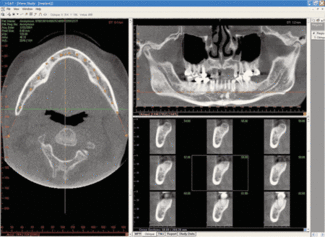

Cone beam

Cone beam or 3-D imaging is the new frontier for digital radiography. While these systems go by many different names, the best way to describe the system is that it’s a cross between a digital pan/ceph and a CAT scan machine. The most popular model right now in the United States is the i-Cat by Imaging Sciences. While I could describe the system in detail, this excerpt from an i-Cat user does the best job of explaining why they are becoming so popular: “Compared to medical scanners, cone beam scanning is 10 times more accurate while reducing a patient’s exposure to radiation by more than 95 percent. Pre-surgical implant treatment planning, preparing to remove impacted third molars, determining how sinus grafts and ridge augmentations have healed, and determining the ideal position for single-tooth replacements are just some of the benefits of cone beam scanning technology. Since cone beam scanning permits multiple slices through the axial, sagittal and coronal views, it removes the guesswork in many situations, such as when it is critical to determine the width of edentulous ridges, whether or not cancellous bone exists between cortical plates, the position of supernumerary and developing tooth buds, whether sockets have filled with bones, if irregularities exist to the condyles, where the mandibular nerve is relative to an impacted tooth and implant sites, or to visualize the borders of a cyst or tumor. Cone beam scanning has an added benefit of being able to take the maxilla and mandible in a single scan.”

Probably the biggest drawback to these systems is the initial cost: around $170,000 to $200,000 each. Dentists all over the country are grouping together to create imaging centers and share the costs of the machines. The cone beam may eventually be the standard of care for many procedures.